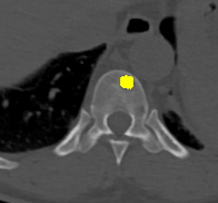

Figure 2: Qualitative results of bone lesion detection. Each column shows a cropped slice with the top row displaying ground-truth (green) and the bottom row showing nnUNet predictions (yellow). (a) shows a TP osteolytic lesion; (b) shows the prediction of a real osteoblastic lesion that was not prospectively marked as ground-truth (before review), and after GT review, it was correctly considered as ground-truth; (c) shows an osteolytic lesion not annotated in ground-truth before review and correctly marked afterwards. A FN adjacent to it is also shown. (d) shows a rare FP on the cortex of a rib.

Results. Qualitative and quantitative results of our model are presented in Fig. 2 and Table 1 respectively. Our model achieved a precision of 96.7% and a recall of 47.3% for detection of bone lesions (lytic, blastic, and mixed). We observed that the model was very confident in its predictions as demonstrated by the vast number of actual lesion predictions (TPs) compared against the FPs. Despite the high precision, the model was not very sensitive to the detection of bone lesions due to the large number of FNs.